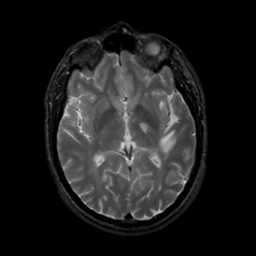

MR Study #13, May 19, 1991 -- Slice #25